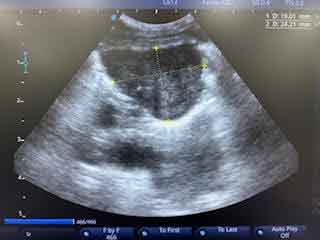

Ultrasound

Ultrasound scanning uses high frequency sound waves to generate images of internal structures. When the sound waves are pointed at the body, some of the waves are absorbed, and some bounce back. The ones that bounce back are measured by the machine and processed into an image for us to examine. It’s possible that your pet’s fur may obstruct the ultrasound scan, so do not be alarmed if your pet comes home with a shaved patch!